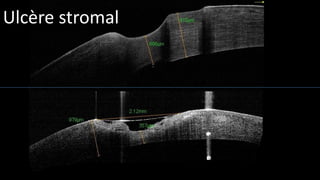

Ulcère stromal

• #14 In chronic superficial ulcerations, the thickness of the epithelium is increased and we observe zones of detachement and an increased density of the proximal stroma. These observations are similar to those collected with traditionnal histology. When the ulceration is deeper, we oberve an increased density of the stroma around the ulceration. The depth of stromal involvement can be measured, and we can see a localized corneal fibrosis made visible by the increase of the corneal density with a strong absorption of the IR beam.